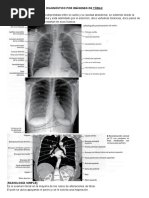

a de la Early Solid Tissue Enhancement dentro de la lesión y otra e Figura 2: Gráfico que representa las diferencias visuales entre curvas de tiempo-intensidad de bajo rie

n el miometrio externo, prestando atención para evitar los vasos sgo, riesgo intermedio y alto (TICs). Una curva de tiempo-intensidad de bajo riesgo se define como un

aumento en la intensidad de la señal del tejido sólido después de la administración de material de con

traste, más lento que en el miometrio, sin un hombro bien definido y sin plataforma. Una curva de tie

denomiosis. Una TIC de bajo riesgo se define como un aumento e mpo-intensidad de riesgo intermedio tiene un aumento inicial moderado en la intensidad de la señal d

n la intensidad del信号 en el tejido sólido después de la administr el tejido sólido, con una pendiente más lenta o igual a la del miometrio, con un hombro y plataforma.

ación de material de contraste, más lento que en el miometrio, sin Una curva de tiempo-intensidad de alto riesgo tiene un aumento inicial rápido en la intensidad de la s

un hombro bien definido y sin plataforma (Figura 2). Una TIC de ri eñal del tejido sólido, con una pendiente mayor que la del miometrio, con un hombro y plataforma.